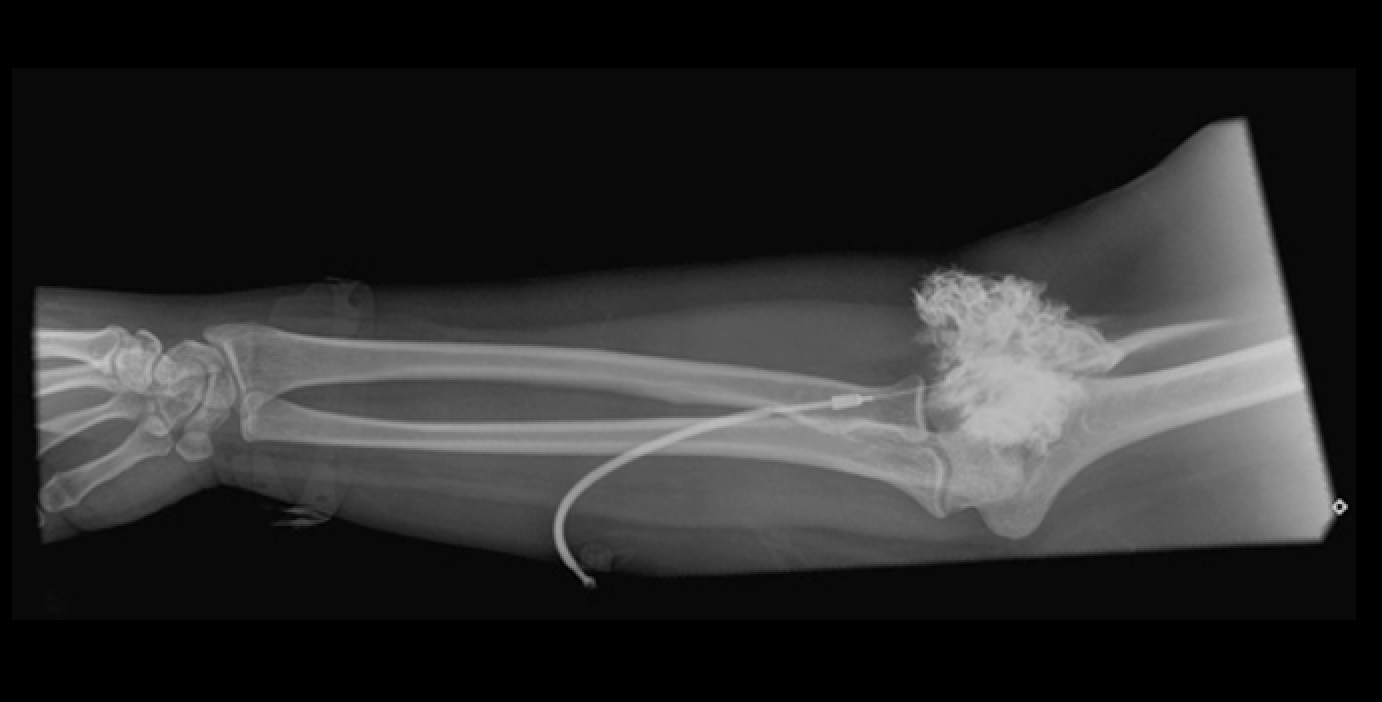

Extravasación del Medio de Contraste.

Imagen (Revista Chilena de Radiología): https://www.scielo.cl/scielo.php?script=sci_arttext&pid=S0717-93082015000400006